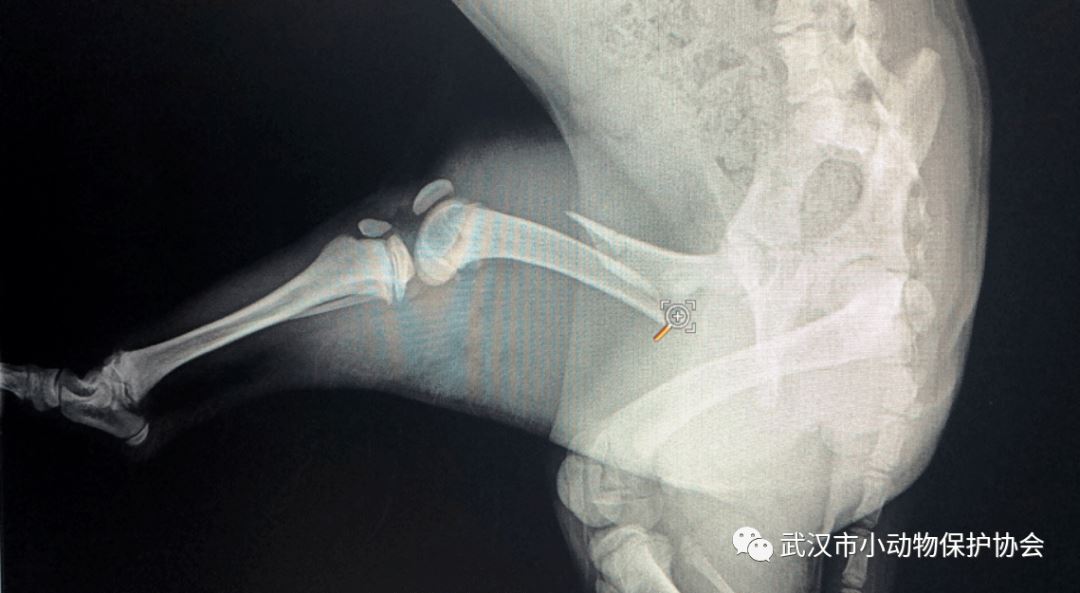

救助经过:一位女士,电话联系协会,在江滩葡轩红酒遇到一只瘫倒在地上的小白狗,可能是被车撞上,随后送往优越医院检查。

江小白的 X光未看到明显骨折,血常规和生化有部分异常指标,考虑车祸导致。住院一周后身体状态好转,恢复正常饮食,继续留观一周后出院。江小白的检查和住院费用是 2000元 。